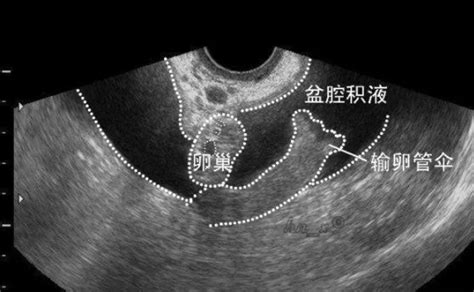

有的女性平时有运动的习惯,但是当检查出有盆腔积液后还能不能继续跑步呢,盆腔积液跑步要注意哪些问题。盆腔积液腿部运动方法可以了解一下。